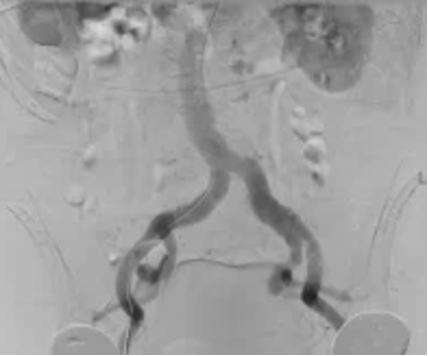

Empiric Colonic Embo Case

Bleeding into diverticulum

Region of bleeding tic

Post embo |